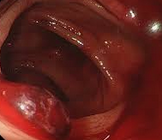

Κολονοσκόπηση που αποκαλύπτει πολυποειδή μάζα που προβάλλει στο μέσο τμήμα της αριστερής κολικής καμπής